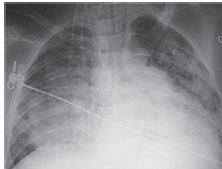

Homem de 58 anos procurou assistência médica devido a dor em hemitórax esquerdo há 10 dias. Ausculta pulmonar: normal; turgência jugular 3+/4+. Radiografia de tórax a seguir.

Enunciado 3309343-1

Nesse momento, é correto afirmar: